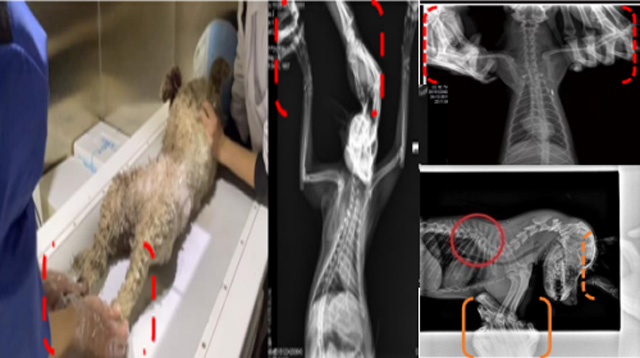

現(xiàn)在寵物醫(yī)療設(shè)備得到高速發(fā)展,現(xiàn)在有越來越多的寵物診療機構(gòu)配置X射線裝置如寵物DR。寵物骨折或者有其他疾病不能通過直觀看出來的。寵物診所醫(yī)生都會使用寵物DR來做輔助檢查。但是有時候?qū)櫸镝t(yī)生沒有加強防護,就在寵物DR室給寵物拍X片做檢查。這樣也是會受到X射線的輻射。因為X射線上崗是屬于職業(yè)病危害崗位。長期的輻射會對人體造成一定的危害。寵物醫(yī)生也需要接受X射線照射的上崗前都必須進行放射工作人員的職業(yè)健康體檢。體檢不合格的話是不能擔任放射工作的。未經(jīng)上崗前職業(yè)健康體檢的勞動者從事接觸職業(yè)病危害作業(yè)的行為,已經(jīng)違反了《中華人民共和國職業(yè)病防治法》第三十五條規(guī)定,依據(jù)《中華人民共和國職業(yè)病防治法》第七十五條規(guī)定,需要進行整改罰款。開展寵物放射診療活動,在日常工作中,對本機構(gòu)的X射線危害的職業(yè)病防治,需要知道并做到以下內(nèi)容: